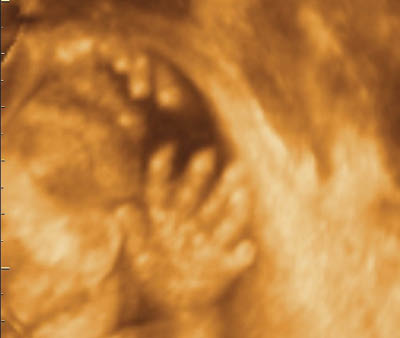

careful examination of the hands and feet are very helpful as most of the cases with trisomy 18 are associated with limb posture abnormalities

Polydactyly is the presence of an extra finger or toe. It is more common in Black women and two types are recognized: type A is when the extra digit is well developed, whereas in type B the extra digit is rudimentary with only soft tissue and no skeletal structure [36]. The extra digit can be preaxial (radial or tibial side) or postaxial (ulnar or fibular side).

Polydactyly may be present as part of a syndrome or as an isolated finding. It is sometimes familial, so family history is very helpful to exclude the association with other abnormalities. Chromosomal study may be offered if there is no familial history of polydactyly. Patients should be informed that fetuses with an isolated finding of polydactyly usually have a favorable outcome, however, parents should also be informed that at present it is not possible to definitely exclude the possibility of a rare anomaly, such as Bardet-Biedl syndrome [36].

Perform an anatomic survey, including a detailed examination for other limb abnormalities.